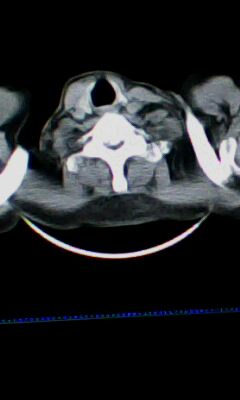

标题: CT25675:男 71 肺癌部分切除术后 3年 [打印本页]

标题: CT25675:男 71 肺癌部分切除术后 3年

两肺感染性病变,右侧肺膨胀不全,左侧上叶结节影及左侧颈部淋巴结肿大建议复查。